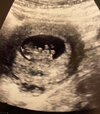

Nie dawało mi spokoju to, ze dziś jestem 8+4, wizytę mam 22go grudnia i wtedy będę 10+3, a lekarz nic o prenatalnych nie wspomniał. Ponadto 22go mnie Pani w recepcji zapisała na konsultacje bez usg.

Zadzwoniłam powiedziałam żeby mi zmieniła 22go na usg i pogadałam z nia trochę. Zapisała mnie 5 stycznia na prenatalne i wtedy będę mogła Pappa ewentualnie zrobić, a 22go omowie to z lekarzem. Dobrze, ze zadzwoniłam bo terminów już nie było.